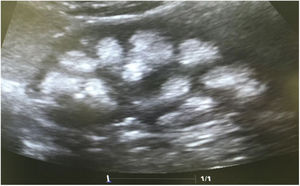

Paciente masculino de 8 años y 11 meses de edad sin antecedentes perinatales de importancia (peso 2,9kg, talla 50cm y Apgar 9/10). Avidez por el agua y la sal desde los 2 años de edad, aproximadamente. Precisó 3 hospitalizaciones durante su primer año de vida por episodios de deshidratación moderada. Acudió hasta en 24 ocasiones al servicio de urgencias de su localidad por la presencia de fiebre. En algunas ocasiones se catalogó de infección de vías respiratorias, si bien, en la mayoría de los casos no se detectó una causa aparente de la misma. Al efectuarse el diagnóstico de ATRd a su hermana, se realizó el abordaje diagnóstico. Su peso era 18kg (percentil 5) y la talla 111cm (percentil 3). Se observó acidosis metabólica hiperclorémica con anión restante normal, hipercalciuria, hipocitraturia severa (tabla 2) y nefrocalcinosis grado III. La valoración audiológica fue normal. La pCO2 urinaria máxima también fue normal (tabla 3). También, después de tres años de tratamiento con álcalis han mejorado tanto el peso (23kg, percentil 8) como la talla (122cm, percentil 17). Recibe tratamiento con citrato de potasio (5mEq/kg/día). El estudio genético mostró la misma mutación que su madre y su hermana.

Ecografía realizada a la madre de los pacientes. Riñones con ecogenicidad heterogénea a expensas de un aumento de la ecogenicidad de las pirámides renales compatible con nefrocalcinosis medular bilateral grado II-III. La relación córtico medular es poco nítida, con datos de nefropatía crónica difusa.